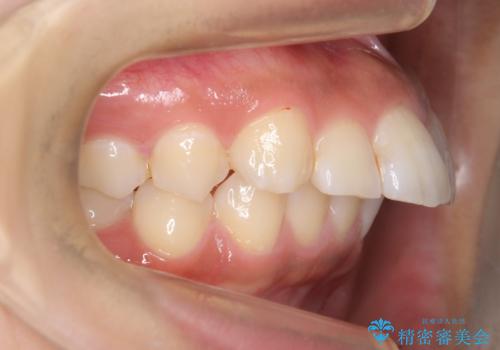

前歯をきれいに 20代女性

- 前歯のがたがたを主訴に来院。

虫歯が多く、矯正治療前に虫歯の治療を行いました。